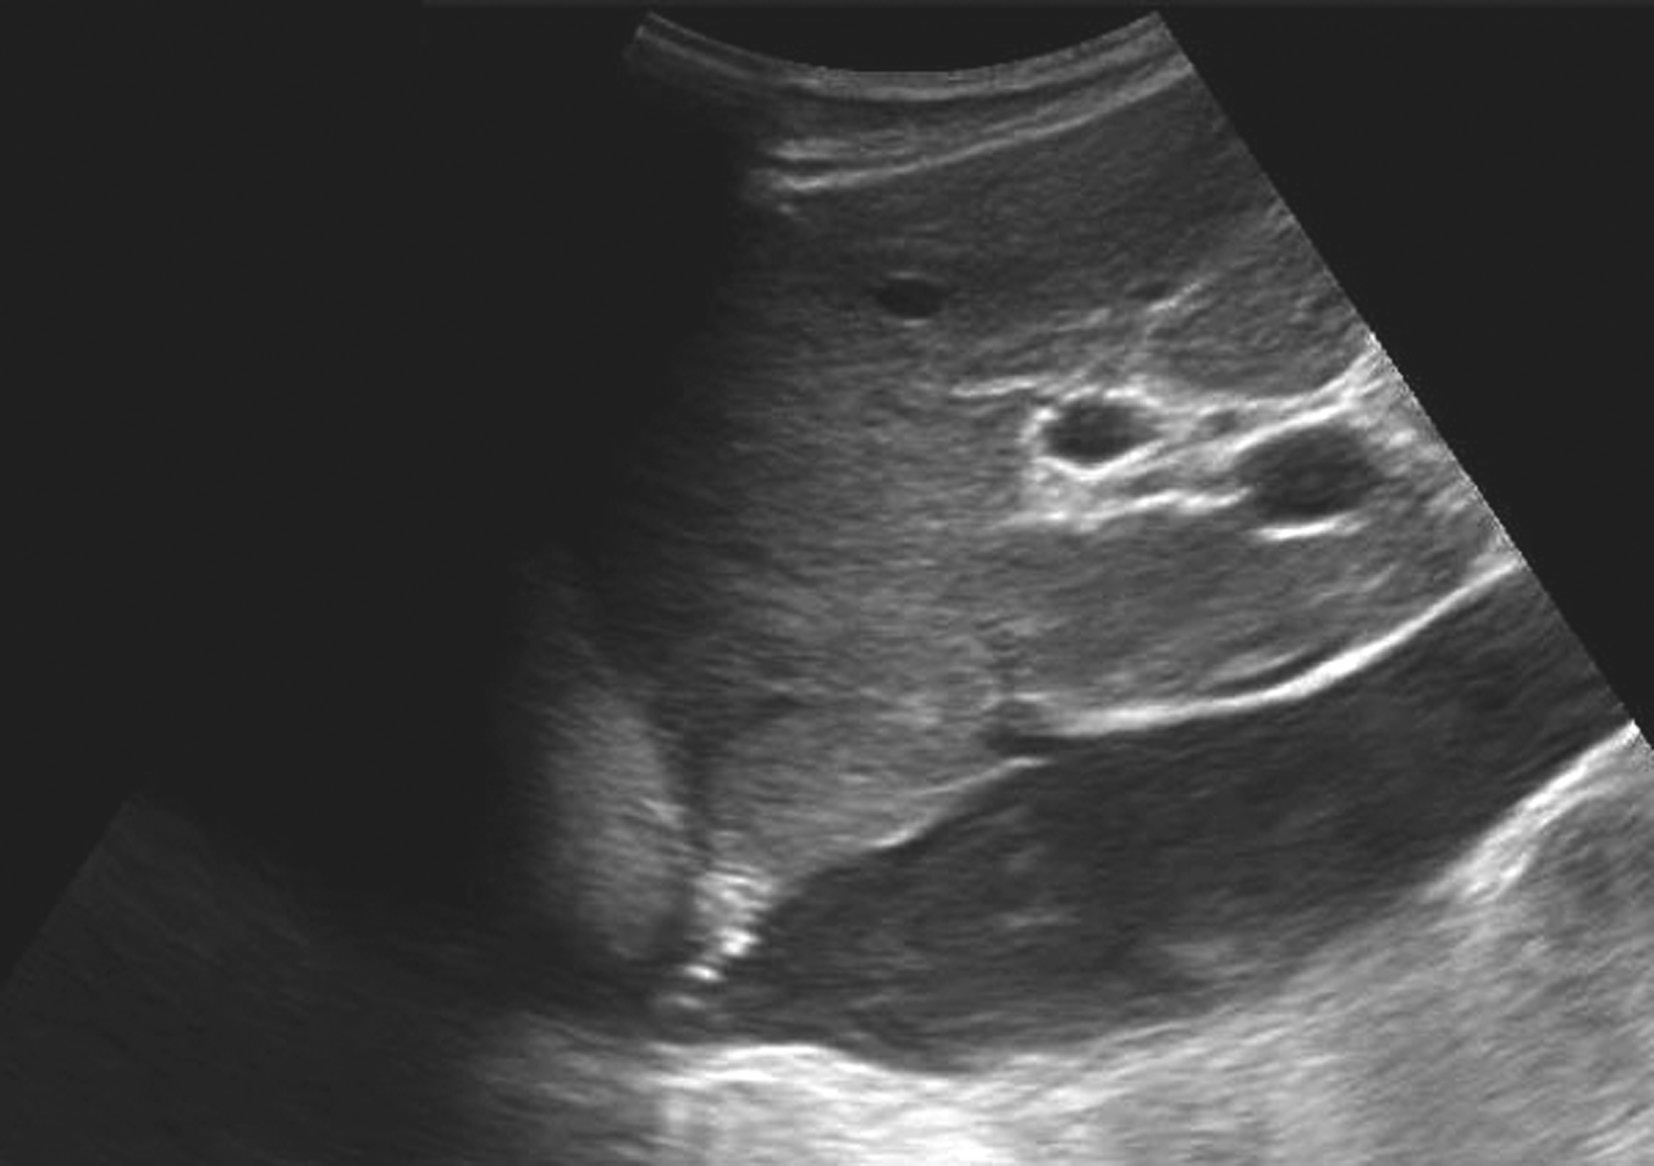

【声像图表现】

(1)灰阶超声:

肝门区结构紊乱,肝外门静脉周围或管腔内可见多条弯曲成团的血管,呈蜂窝状或网格状无回声区结构,在结构紊乱的肝门部仔细辨认可见管腔狭窄、壁增厚回声增强的门静脉管道,管腔内可见癌栓或血栓,部分可压迫胆道系统造成肝内外胆管扩张。可出现继发门静脉高压声像图改变,如脾肿大、脾静脉及肠系膜上静脉增宽,严重者可见腹水。

(2)彩色多普勒血流显像:

在肝门区蜂窝状或网格状无回声区结构内充满色彩暗淡的彩色血流信号;门静脉狭窄者于门静脉内探及少许连续性彩色血流通过,其周围蜂窝状液性无回声区呈红、蓝相间的不连续彩色血流信号;完全闭塞或栓子充填的门静脉内则无彩色血流信号显示;如图5-21-26所示。